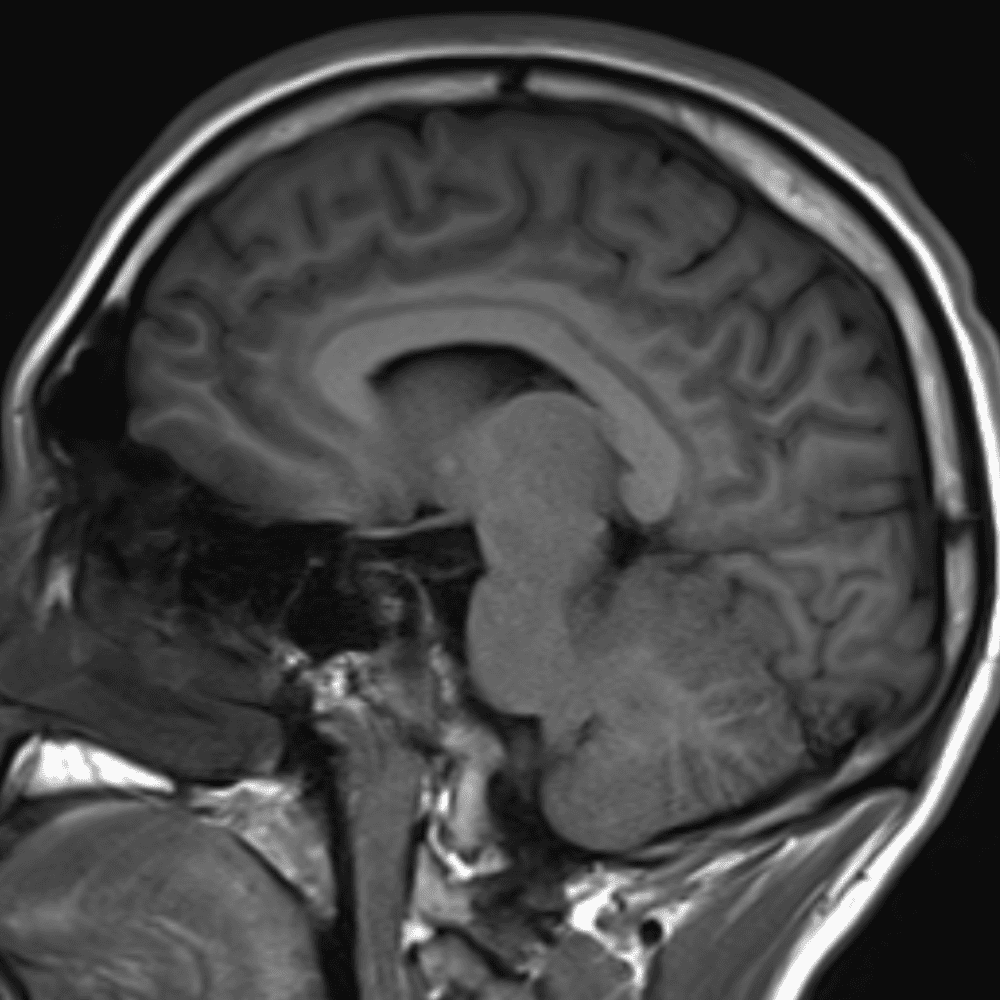

๋ฏธ๋ฌ˜ํ•˜๊ฑฐ๋‚˜ ์–ด๋ ค์šด ์‚ฌ๋ก€์™€ ์ผ๋ถ€ ์ •์ƒ ์‚ฌ๋ก€๋ฅผ ํฌํ•จํ•˜์—ฌ ๋‹น์ง์„ ์‹œ๋ฎฌ๋ ˆ์ด์…˜ํ•ฉ๋‹ˆ๋‹ค.

50 ์‚ฌ๋ก€